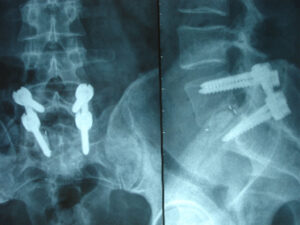

Stabilisierungsoperationen (Spondylodese, Fixateur interne) bei degenerativen Veränderungen und nach Traumata der LWS

Mit zunehmendem Alter kommt es durch Alterungsprozesse bei relativ vielen Menschen nicht nur zu Verengungen des Wirbelkanals, sondern auch zu Instabilitäten (sog. Gleitwirbel (Spondylolisthesis)) oder Skoliosen (S‑förmige Krümmung der Wirbelsäule). In bestimmten Fällen führt dies zu heftigen Schmerzen im Rücken und/oder in den Beinen, so dass die Gehstrecke immer weiter reduziert wird.

Diese Instabilitäten können zu einer Zunahme von Verengungen des Wirbelkanals (Spinalstenose) oder der Austrittslöcher von Nervenwurzeln (Foramenstenosen) führen.

Bei hohem Leidensdruck empfiehlt sich schließlich eine Operation. Das Wirbelgleiten ist dabei nur durch eine aufwendige Operation zu therapieren, bei der die Wirbel mit einem Schrauben-Stab-System (Fixateur interne) miteinander fixiert werden. Der Bandscheibenraum wird zusätzlich ein- oder beidseitig ausgeräumt und mit Knochen und einem Platzhalter (Cage) mit dem Ziel gefüllt, dass die Wirbel im Verlauf knöchern verschmelzen (Fusion). Teilweise ist eine spätere Entfernung der Implantate bei einfacheren Traumata und sicheren Fusionen denkbar.

Auch bei sich wiederholenden Bandscheibenvorfällen in der gleichen Bandscheibenetage können Stabilisierungsoperationen zur Vermeidung rezidivierender Bandscheibenvorfälle angezeigt sein.

Für Frakturen der LWS und BWS sind Stabilisierungsoperationen ebenfalls häufig erforderlich.

Bilder:

Roentgen: 2 Höhen Spondylodese

Roentgen: Spondylodese LW5/SW1